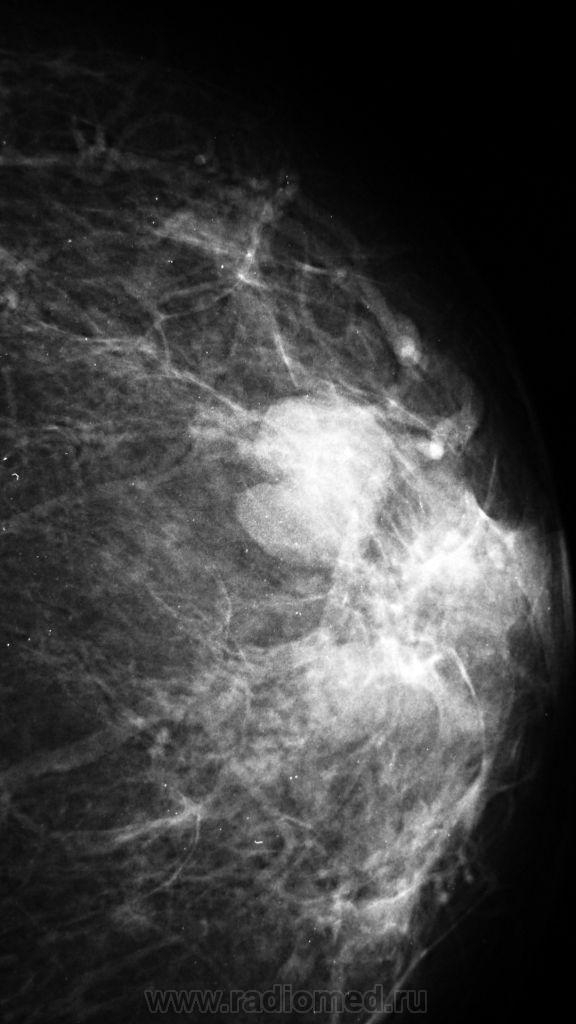

Фиброаденома или киста?

Или как всегда только гистология...

Больше похоже на кисту, но всё же поможет в диф.диагностике узи молочных желез

У меня возникло недоверие к участку, помеченному стрелками, а главное у "лучикам".

Помеченный участок, мне видится не подозрительным на neo процесс

А, я бы придралься с учетом выраженного расширения отдельного сосуда.

В другой железе так же  не большие овальные образования скорее всего кисты. По общепринятой тактике - назначается УЗИ, если простая киста - удаляется содержимое, вводится воздух(онкологом, врачем УЗИ, хирургом,  где, кто выполняет эту процедуру), далее пневмоцистография (к-к и мед -лат проекции) для подтверждения отсутствия внутриполстных образований и контроля удаления содержимого, если все нормально - наблюдение, Если при УЗИ образование тканное, или стенки кисты толстые, не равномерные, имеются внуирипролостные компоненты -  удаление с гистологией. Мелкие кисты подлежат наблюдению.

Спасибо за советы. т.е, как я понял, скиалогически предположить киста или фибрааденома, когда нет кальцификации, не представляется возможным.

Вы абсолютно правы